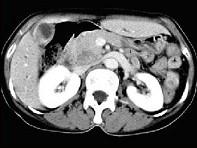

问题 患者,男,51岁,右上腹隐痛两月余,CT扫描如图,最可能的诊断是()

选项 A.胆囊癌伴肝门胰头周围转移 B.胆囊息肉 C.胆囊黄色肉芽肿 D.慢性胰腺炎并胆囊息肉 E.胆囊腺瘤及慢性胰腺炎

答案 A